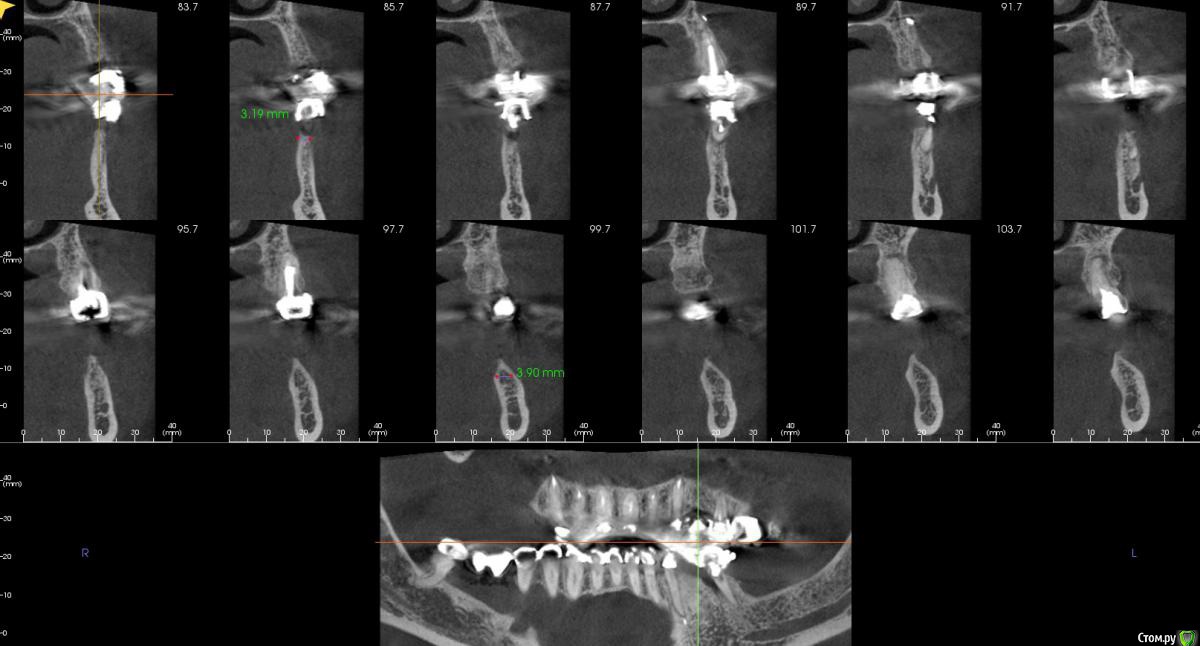

kamranchick Опубликовано 3 ноября, 2018 Автор Поделиться Опубликовано 3 ноября, 2018 вот еще такие реформаты Ссылка на комментарий

Bier Опубликовано 3 ноября, 2018 Поделиться Опубликовано 3 ноября, 2018 блин, Камранчик, я вообще не понимаю в какую зону ты хочешь ставить и как твою нарезку прикрепить к панораме, которая ниже. Никакой системы координат нет.Короче там, где гребень 4.7 - можно крутить и не делать пластик. Ссылка на комментарий

Дмитрий Л. Опубликовано 3 ноября, 2018 Поделиться Опубликовано 3 ноября, 2018 Короче там, где гребень 4.7 - можно крутить и не делать пластик.Провокативно.3,5 в моляр? Ссылка на комментарий

Irouil Опубликовано 3 ноября, 2018 Поделиться Опубликовано 3 ноября, 2018 не совсем понял твою мыслю))После редукции до ширины гребня 4 мм крутить 3.5 ориентируясь на язычную стенку, если торчит только краешек 1 мм вестибулярно то бугром 1 Ссылка на комментарий

Bier Опубликовано 4 ноября, 2018 Поделиться Опубликовано 4 ноября, 2018 После редукции до ширины гребня 4 мм крутить 3.5 ориентируясь на язычную стенку, если торчит только краешек 1 мм вестибулярно то бугромредуцировать не надо, надо заглублять. Апроксимальные костные пики обеспечат стабильность мягких тканей. 2 Ссылка на комментарий